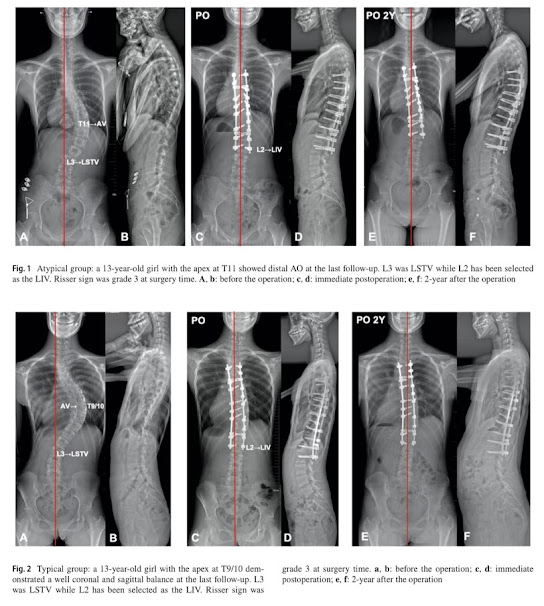

La curva atípica de Lenke 1A tenía sus propias características radiográficas. Era más probable que se desarrollara AO cuando LIV era proximal a LSTV, lo que indicaba que se debían considerar diferentes niveles de fusión en estos dos subtipos de Lenke 1A. Recomendamos la última vértebra sustancialmente en contacto (LSTV) como LIV en casos atípicos de Lenke 1A, mientras que un nivel proximal a LSTV podría estar disponible en la curva típica de Lenke 1A.